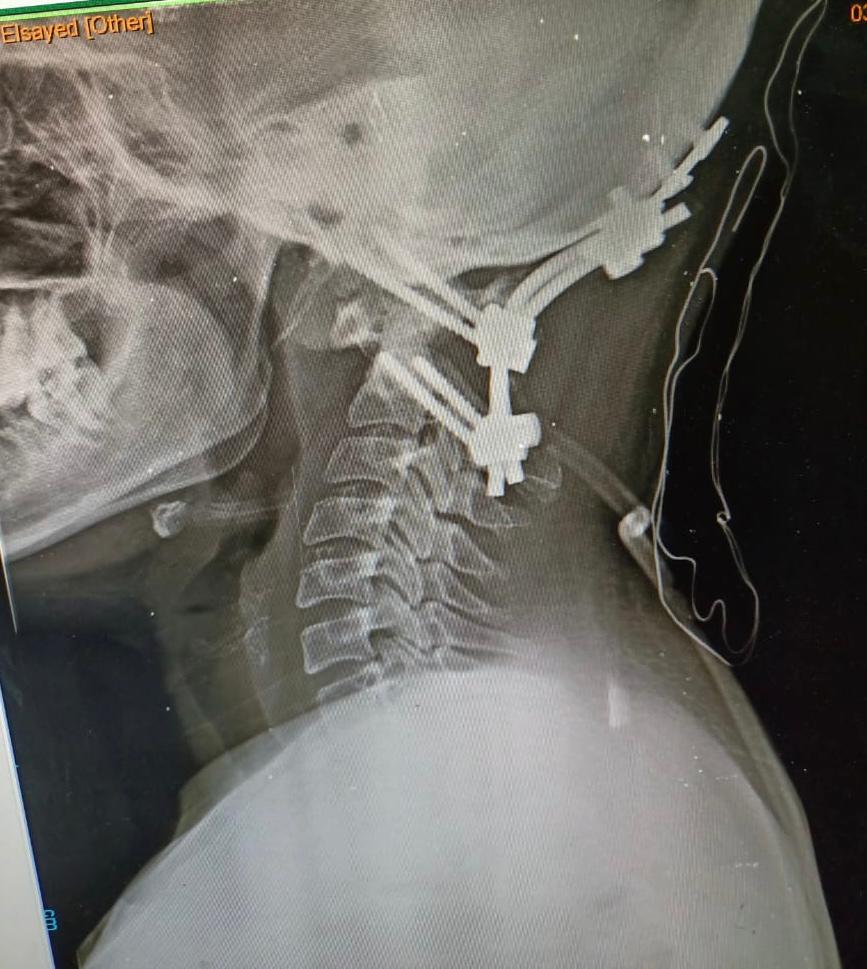

وقال الدكتور مجدي أمين القاضي عميد كلية الطب البشري ورئيس مجلس إدارة المستشفيات الجامعية، إنه تم على الفور حجز المريضة بالقسم والتجهيز للتدخل الجراحي لتوسيع قاع الجمجمة مع استعدال الاعوجاج الفقرات العنقية وإعادتها إلى الوضع التشريحي الطبيعي وتثبيتها بقاع الجمجمة.

وذكر الدكتور حمدي سعد المدير التنفيذي للمستشفيات الجامعية، أنه تم خروج المريضة من غرفة العمليات إلى العناية المركزة لمتابعة الوظائف الحيوية، والتي أثبتت استقرار حالتها والتحسن في الحركة على مستوى الأطراف الأربعة، وتم خروج المريضة من العناية المركزة إلى القسم الداخلي لتستطيع المشي بعد مرور شهر وهى طريحة الفراش.